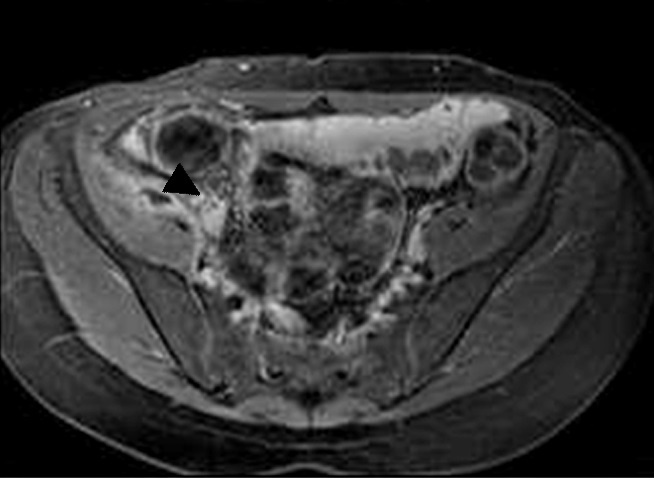

Figura 3

Enfermedad de Crohn a) Secuencia T2 axial sin supresión grasa evidencia engrosamiento parietal de la última asa ileal (flecha blanca).

b y c) secuencias T1 con saturación grasa y gadolinio. Realce estrajpgicado dado por realce de la mucosa (flecha larga) y serosa (flecha corta) separadas por la capa submucosa edematosa (asterisco).